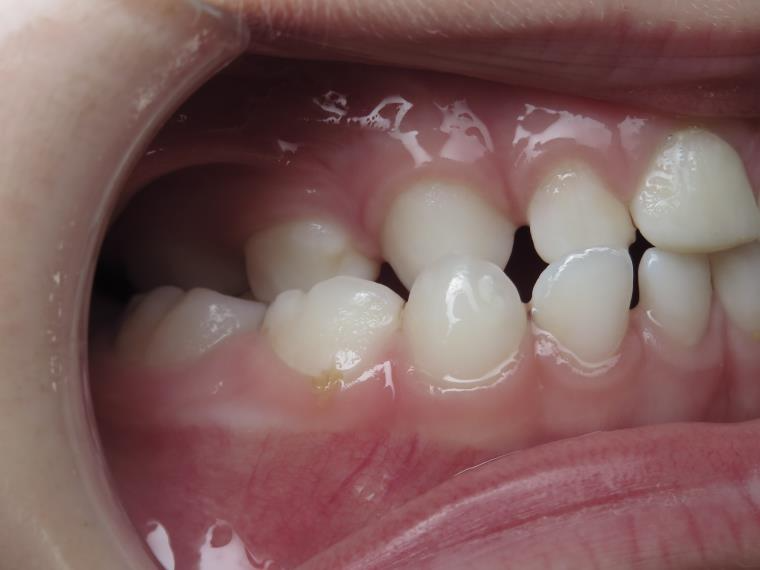

inversion des dents postérieur coté droit

appareillage mobile pendant 13 mois